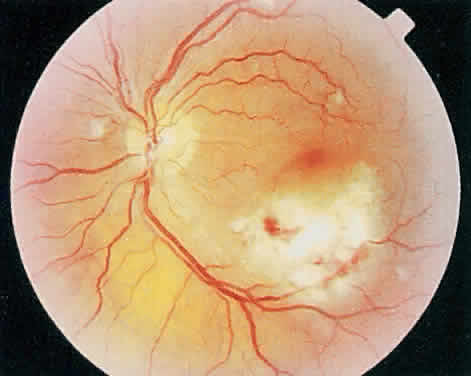

Fig. 3. Active cytomegalovirus retinitis adjacent to the optic nerve. Visual acuity was counting fingers.

Fig. 4. Three months later the retinitis has completely destroyed the retina leaving a visual acuity of no light perception.